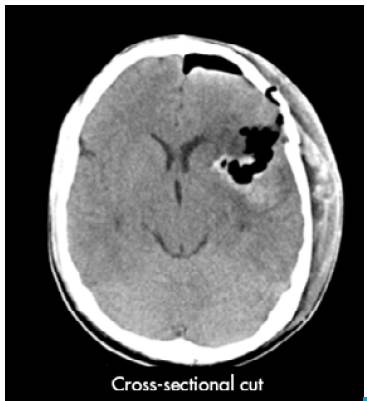

An emergency craniotomy for drainage was scheduled based on the results of the CT scan. Craniotomy showed a yellowish, hard tumor mass with necrosis and suggestive of astrocytoma. The patient did not require antibiotic management after the procedure and a new CT scan was requested, which showed satisfactory tumor resection with residual perilesional edema, without deviation from the midline (Figure 2). The histopathological study described resection compatible with glioblastoma (Figure 3).

Malignant gliomas represent 35-45% of all adult brain tumors and about 85% of them are glioblastomas; therefore, glioblastomas represent 29.7-38.2% of all brain tumors in adults. 12,16 In turn, gliosarcoma represents about 2% of all glioblastomas and 0.59-0.76% of all adult brain tumors 10; it is usually found in the supratentorial region with a slight preference for the temporal lobes 8, although it can affect the frontal, parietal or occipital lobes and corpus callosum less frequently. 17 Its clinical profile may include an intracranial hypertension syndrome such as headache, dizziness, vomiting, papilledema, seizures and motor deficit. CT usually shows a well-defined hyperdense lesion with marked perilesional edema, necrotic areas, and mass effect. 18